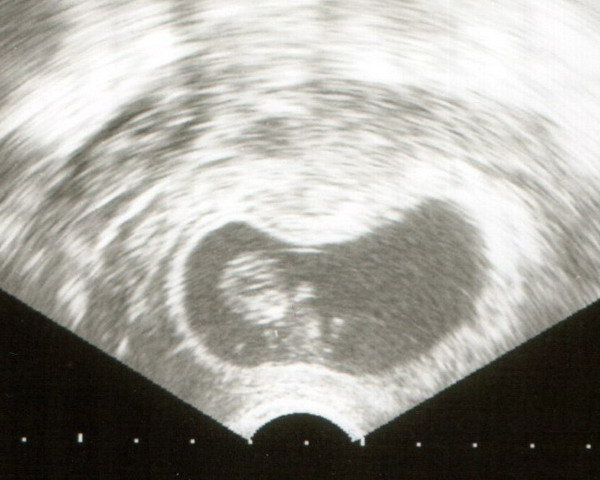

Baba 9+3

Baba 9+3